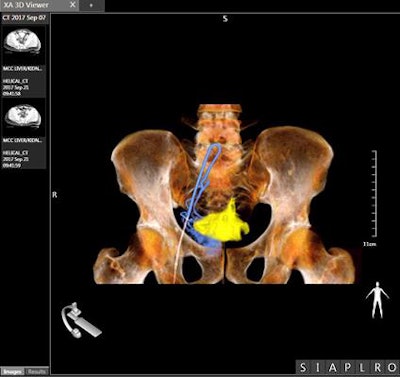

An interventional suite that pairs an angiography system with a CT scanner -- called Alphenix 4D CT -- also is being demonstrated at the vendor's booth. The suite matches an Alphenix Sky + C-arm with an Aquilion One Genesis volumetric CT scanner, enabling clinicians to plan, verify, and treat patients in a single session.